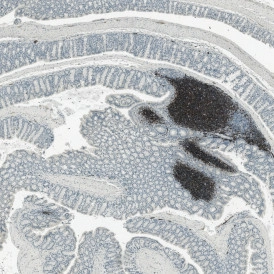

Creating effective treatments relies on understanding the pathophysiology of CIDs. One key method of studying CIDs is brightfield microscopy combined with tissue staining. A brightfield slide scanner can offer high-resolution digitized image of tissue samples stained to highlight specific cellular structures and components.

Brightfield slide scanning is a powerful tool in CID research. Utilizing a system like TissueFAXS PLUS can provide whole-slide images of the entire tissue architecture. For example, hematoxylin and eosin (H&E) staining is commonly used to highlight nuclei and cytoplasmic elements. It delivers clear images of cellular morphology and tissue organization. This is essential in identifying pathological changes associated with chronic inflammation, such as cellular infiltration, tissue remodeling, and fibrosis.